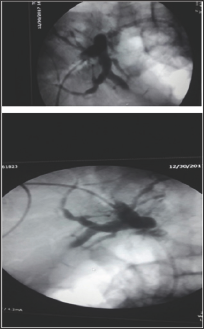

Figure 2: A tight Anastomotic stricture by percutaneous injection.

Figure 3: External Drain and internal CBD stent in place.

Figure 4: Post External and drain placement.

During ERCP cannulation was performed using standard method and accessories. The distal CBD was of a diameter of 0.8 cm and a tight stricture almost at the anastomosis where the guidewire could not be passed more proximally through the very tight stricture by any means [7]. So, the decision was to proceed with Rendezvous procedure with the aid of interventional radiologist. The percutaneous puncture was performed aided by ultrasound and access was gained into the mildly dilated right hepatic bile duct. The guidewire was introduced through the right intrahepatic duct through the anastomosis, where after few trials the wire had been passed through the stricture into CBD then out of the ampulla of vater. Then, using the duodenoscope the wire coming out the ampulla of vater was pulled into the scope channel and a sphincterotome was passed over the guidewire into CBD then across the stricture successfully. Finally a plastic stent of 7 F*7 cm was inserted successfully through the stricture with good bile drain. The percutaneous rendezvous procedure enabled placement of an internal-external drain [8]. One week after the procedure the patient reported having right sided chest pain along with progressive shortness of breath. The chest Xray showed a massive right sided pleural effusion. Paracenthesis revealed an exudative bilious fluid. The external drain was removed followed by replacement of a longer new internal plastic stent placement. The right pleural fluid reacumulation was diminished significantly and the patients shortness of breath improved dramatically (Figures 1-4).